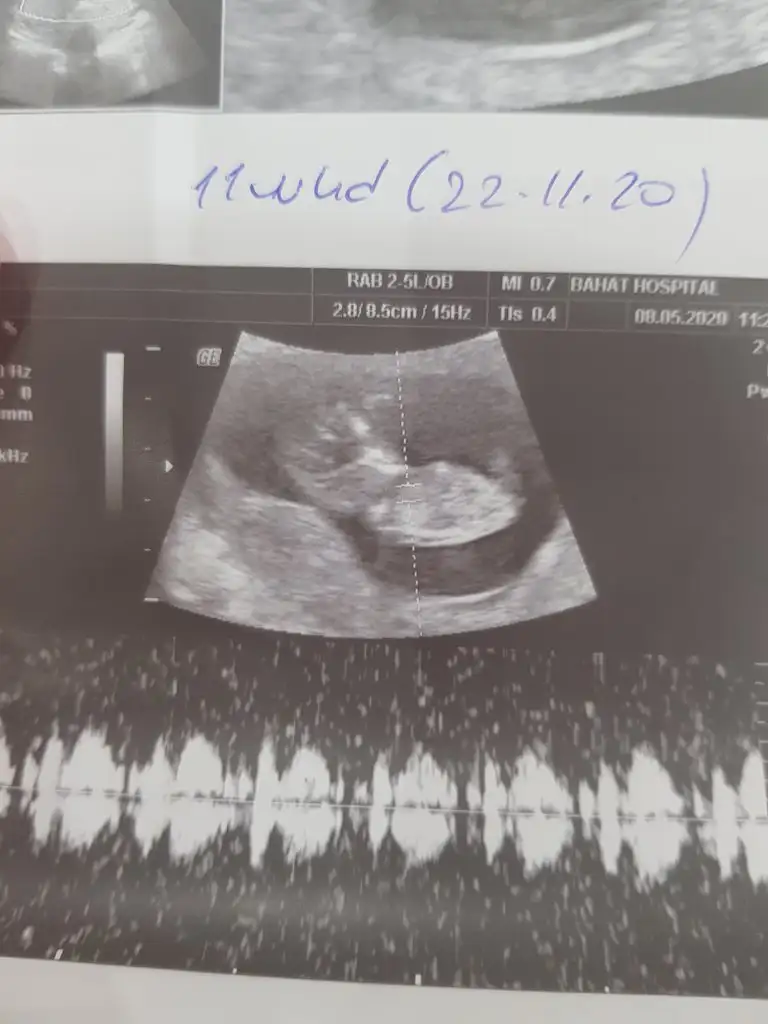

Bize de bi tahminde bulunur musunuz

Eklentiler

• 20200508_161448.webp

20200508_161448.webp

24,1 KB · Görüntüleme: 68

Kaç haftalık 11 12 13 hafta olmalı usg çok ner değil eminde olamadım sanki kız gibi siz tekrar usg paylaşın